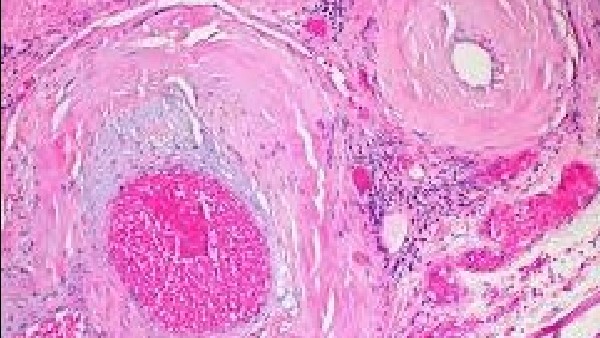

ಸಾಮಾನ್ಯವಾಗಿ ಈ ಅಮಿಲೋಯ್ಡೋಸಿಸ್ ಎನ್ನುವುದು ದೇಹದಾದ್ಯಂತ ಅಂಗಗಳು ಮತ್ತು ಅಂಗಾಂಶಗಳಲ್ಲಿ ಅಮಿಲಾಯ್ಡ್ ಎಂಬ ಅಸಹಜ ಪ್ರೋಟೀನ್ನ ರಚನೆಯಿಂದ ಉಂಟಾಗುವ ಅಪರೂಪದ, ಗಂಭೀರ ಪರಿಸ್ಥಿತಿಗಳನ್ನು ಸೃಷ್ಟಿಸುವ ಗುಂಪಿನ ಹೆಸರಾಗಿದೆ. ಅಮಿಲಾಯ್ಡ್ ಮೂಳೆ ಮಜ್ಜೆಯಲ್ಲಿ ಉತ್ಪತ್ತಿಯಾಗುವ ಅಸಹಜ ಪ್ರೋಟೀನ್ ಆಗಿದೆ. ಯಾವುದೇ ಅಂಗಾಂಶ ಅಥವಾ ಅಂಗದಲ್ಲಿ ಇದು ಹುಟ್ಟಿಕೊಳ್ಳಬಹುದು. ಅಮಿಲಾಯ್ಡ್ ಪ್ರೋಟೀನ್ಗಳ ರಚನೆಯಿಂದಾಗಿ ದೇಹದಲ್ಲಿ ಅಂಗಗಳು ಮತ್ತು ಅಂಗಾಂಶಗಳು ಸರಿಯಾಗಿ ಕೆಲಸ ಮಾಡುವುದಕ್ಕೆ ಕಷ್ಟವಾಗತ್ತದೆ. ಯುಕೆಯ ರಾಷ್ಟ್ರೀಯ ಆರೋಗ್ಯ ಸೇವೆ ಪ್ರಕಾರ, ಇದು ಅಂಗಾಂಗ ವೈಫಲ್ಯಕ್ಕೆ ಕಾರಣವಾಗುತ್ತದೆ.

ಎಎಲ್ ಅಮಿಲೋಯ್ಡೋಸಿಸ್ ಮೂಳೆ ಮಜ್ಜೆಯಲ್ಲಿ ಕಂಡುಬರುವ ಕೆಲವು ಜೀವಕೋಶಗಳಲ್ಲಿನ ಅಸಹಜತೆಯಿಂದ ಉಂಟಾಗುತ್ತದೆ. ಇದನ್ನು ಪ್ಲಾಸ್ಮಾ ಜೀವಕೋಶಗಳು ಎಂದು ಕರೆಯಲಾಗುತ್ತದೆ. ಅಸಹಜ ಪ್ಲಾಸ್ಮಾ ಕೋಶಗಳು ಬೆಳಕಿನ ಸರಪಳಿ ಪ್ರೋಟೀನ್ಗಳ ಅಸಹಜ ರೂಪಗಳನ್ನು ಉತ್ಪಾದಿಸುತ್ತವೆ, ಇದು ರಕ್ತಪ್ರವಾಹಕ್ಕೆ ಪ್ರವೇಶಿಸುತ್ತದೆ ಮತ್ತು ಅಮಿಲಾಯ್ಡ್ ಅನ್ನು ರೂಪಿಸುತ್ತದೆ. ಈ ಆರೋಗ್ಯವಂತ ಜನರು ತಮ್ಮ ರಕ್ತದಲ್ಲಿ ಸಾಮಾನ್ಯ ಬೆಳಕಿನ ಸರಪಳಿ ಪ್ರೋಟೀನ್ಗಳನ್ನು ಹೊಂದಿರುತ್ತಾರೆ, ಅದು ಅವರ ನೈಸರ್ಗಿಕ ಪ್ರತಿಕಾಯ ಪ್ರೋಟೀನ್ಗಳ ಭಾಗವಾಗಿರುತ್ತದೆ. ಇವು ದೇಹವನ್ನು ಸೋಂಕಿನಿಂದ ರಕ್ಷಿಸಲು ಸಹಾಯ ಮಾಡುತ್ತವೆ.

AL ಅಮಿಲೋಯ್ಡೋಸಿಸ್ ರೋಗಿಗಳಲ್ಲಿನ ಅಸಹಜ ಬೆಳಕಿನ ಸರಪಳಿಗಳು ಥ್ರೆಡ್ ತರಹದ ರೀತಿಯಲ್ಲಿ (ಅಮಿಲಾಯ್ಡ್ ಫೈಬ್ರಿಲ್ಗಳು) ಒಟ್ಟಿಗೆ ಸೇರಿಕೊಳ್ಳುತ್ತವೆ, ಅದನ್ನು ದೇಹದಿಂದ ಸುಲಭವಾಗಿ ತೆರವುಗೊಳಿಸಲು ಸಾಧ್ಯವಾಗುವುದಿಲ್ಲ. ಕಾಲಾನಂತರದಲ್ಲಿ, ಅಮಿಲಾಯ್ಡ್ ಫೈಬ್ರಿಲ್ಗಳು ಅಂಗಾಂಶಗಳು ಮತ್ತು ಅಂಗಗಳಲ್ಲಿ AL ಅಮಿಲಾಯ್ಡ್ ಅನ್ನು ನಿರ್ಮಿಸುತ್ತವೆ. ಕ್ರಮೇಣ ಇದು ಸರಿಯಾಗಿ ಕಾರ್ಯನಿರ್ವಹಿಸುವುದನ್ನು ನಿಲ್ಲಿಸುತ್ತದೆ, ಹೀಗಾಗಿ AL ಅಮಿಲೋಯ್ಡೋಸಿಸ್ ಹಲವು ರೋಗಲಕ್ಷಣಗಳನ್ನು ಉಂಟುಮಾಡುತ್ತದೆ. ಇತರ ಕೆಲವು ವಿಧದ ಅಮಿಲೋಯ್ಡೋಸಿಸ್ ಗಿಂತ ಭಿನ್ನವಾಗಿ AL ಅಮಿಲೋಯ್ಡೋಸಿಸ್ ಆನುವಂಶಿಕವಾಗಿಲ್ಲ. ಆದ್ದರಿಂದ ಈ ಸ್ಥಿತಿಯನ್ನು ಹೊಂದಿರುವ ವ್ಯಕ್ತಿಯು ಅದನ್ನು ತಮ್ಮ ಮಕ್ಕಳಿಗೆ ರವಾನಿಸಲು ಸಾಧ್ಯವಿಲ್ಲ. ಅದೇ ರೀತಿ ಈ ರೋಗಾಣು ವ್ಯಕ್ತಿಯಿಂದ ವ್ಯಕ್ತಿಗೆ ಹರಡುವಂಥದ್ದೂ ಅಲ್ಲ ಎಂದು ತಜ್ಞರು ಹೇಳುತ್ತಾರೆ.